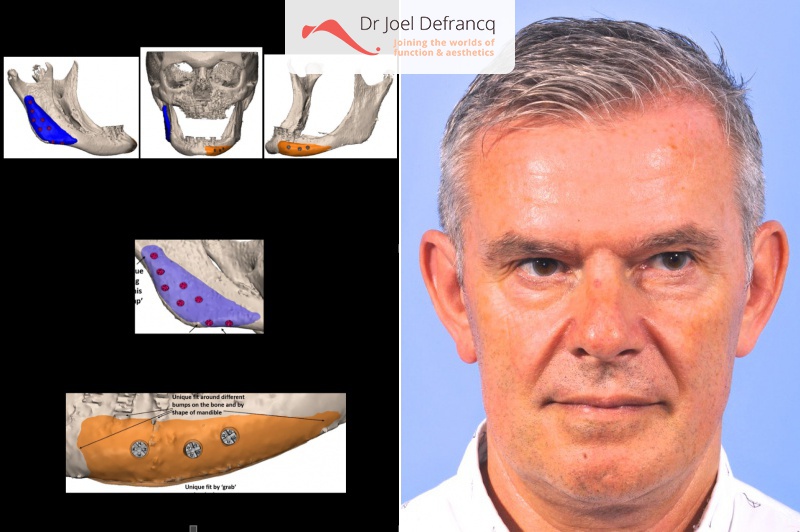

Wannes: Te kleine en te korte bovenkaak. Slecht geplaatste implantaten. Peek implantaten voor de asymmetrie

- Kaakhoek augmentatie